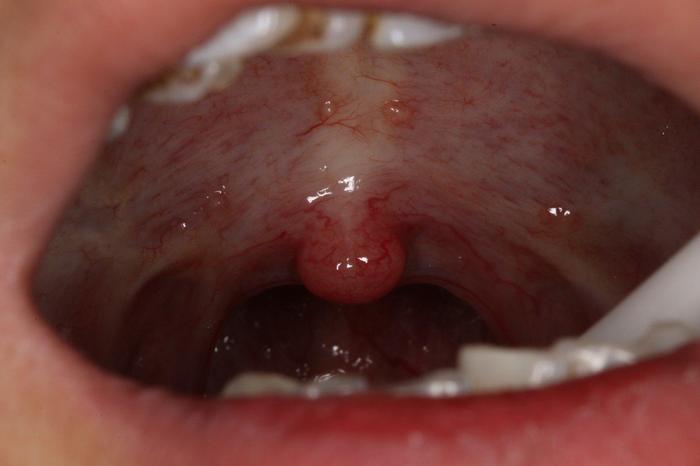

什么是口腔黏膜下纤维化

什么是口腔黏膜纤维化,看完还敢嚼槟榔吗? - 知乎